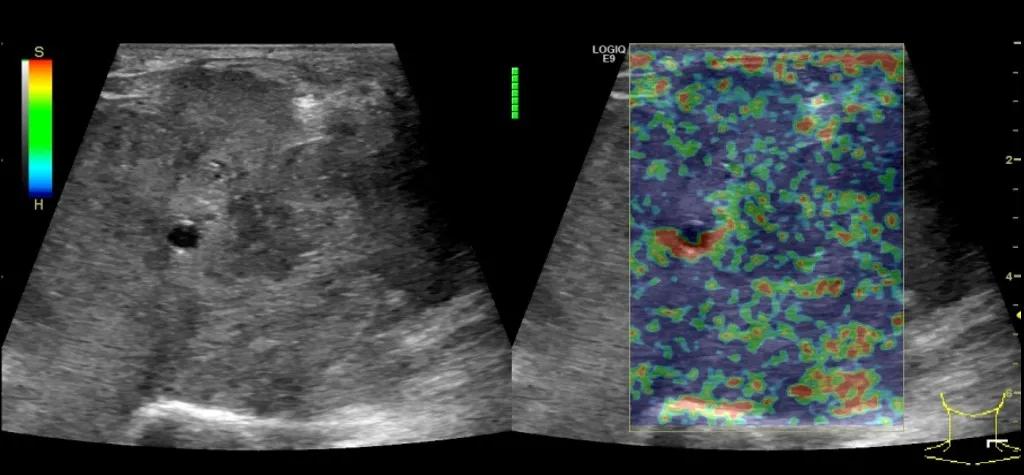

第二例是食管癌患者,术后半年余锁骨上固定淋巴结可触及肿大,疼痛非常明显,系统治疗后无缓解,患者希望通过局部处理缓解症状。造影显示强化信号明显,结节部分区域坏死,故主要针对强化区域从后向前的逐层的消融,皮下进行液体隔离减少烫伤。热消融后影像显示血流增强消失,弹性、硬度增高,一个月后复查显示充盈缺损,完全消融,疗效远超预期。

(病例2图例)